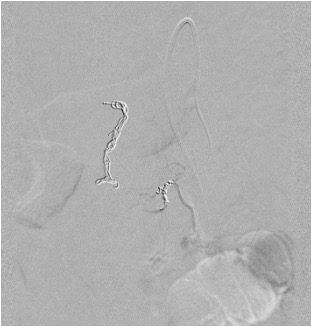

Completion angiogram

Likely cause: Bleeding from jejunal branches, hepaticojejunostomy site, or other post-operative vessels — not from GDA stump itself.

Next step: Repeat angiography — complete celiac + SMA survey. Identify new bleeding source. Targeted superselective embolization of new vessel. Involve surgery early if repeat failure.

- Rebleeding — from non-GDA vessel (jejunal branches, hepaticojejunostomy); requires complete re-survey